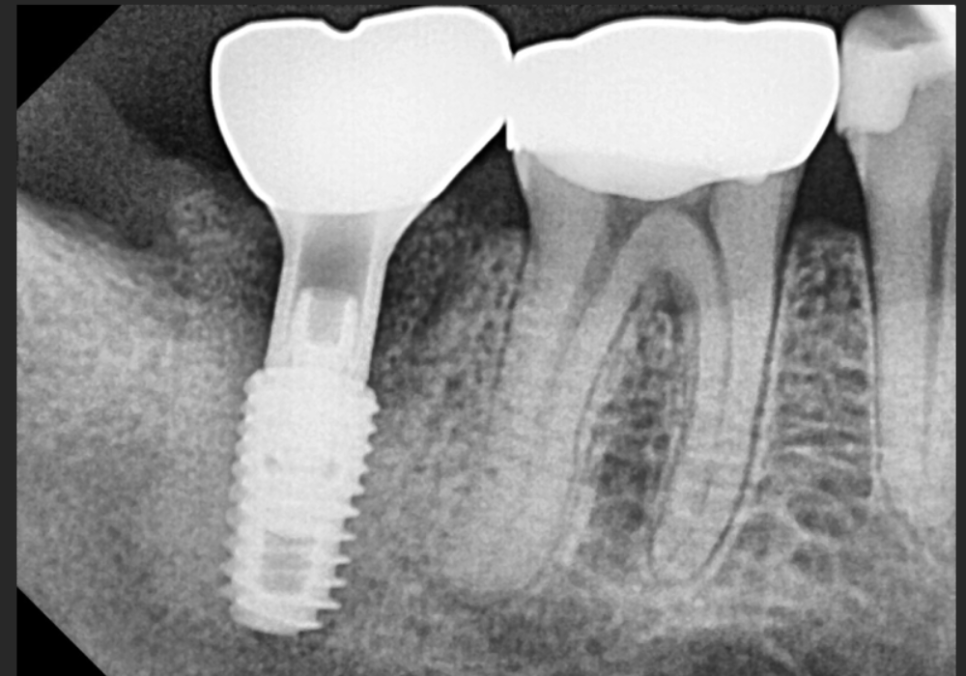

잇몸뼈가 안정적으로

생성된 것을 확인한 뒤,

하치조 신경을 피해 안전하게

잘 식립된 모습입니다.

이 상태로 바로 보철을 올리면 좋겠지만,

임플란트와 뼈가 굳기까지

안전하게 기다려야합니다.

식립 후 2개월 뒤, 임플란트와 뼈가

완전히 하나로 붙은 것을 확인하고

보철까지 성공적으로 완성해 드렸어요.